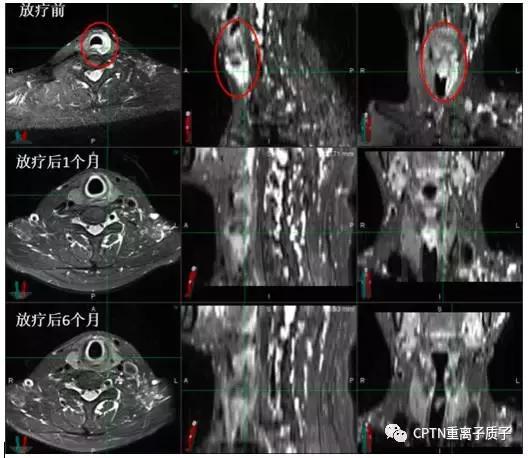

图为高危局限期前列腺癌患者,初诊 PSA最高达21.359ng/ml。既往有高血压、冠心病等内科基础疾病,手术风险大,后行根治性重离子治疗联合内分泌治 疗。治疗结束后复查PSA:0.221ng/ml,复查MRI提示前列腺肿瘤从治疗前2.1*1.9cm缩小到0.8*0.8cm(如图所示,红色圆圈部分)。治疗后半年随访PSA:<0.003ng/ml,治疗及随访过程中未出现尿*禁失**、排尿困难等并发症,可以正常参加各类社会活动。